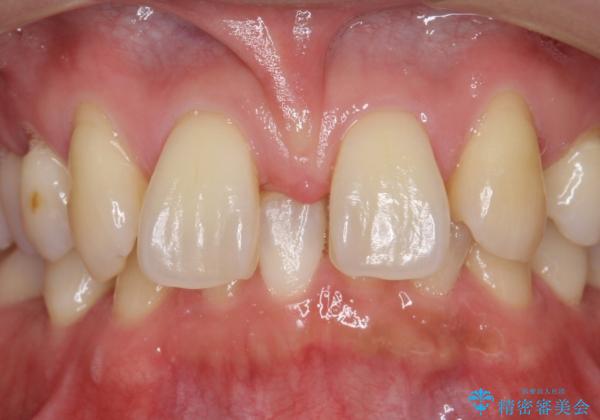

- 前歯部のすきっぱと歯並びが気になるので診て欲しいといらっしゃった方の症例です。

全顎矯正は御希望されなかったため、上顎前歯部のみの部分矯正とオールセラミッククラウンによる補綴を行いました。

- オールセラミッククラウン…¥100,000×6、仮歯…¥10,000×6、部分矯正…¥200,000費用は治療当時の料金となります